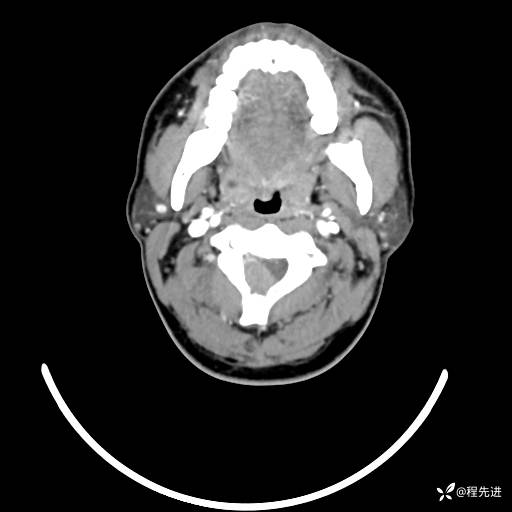

CT平扫+增强: